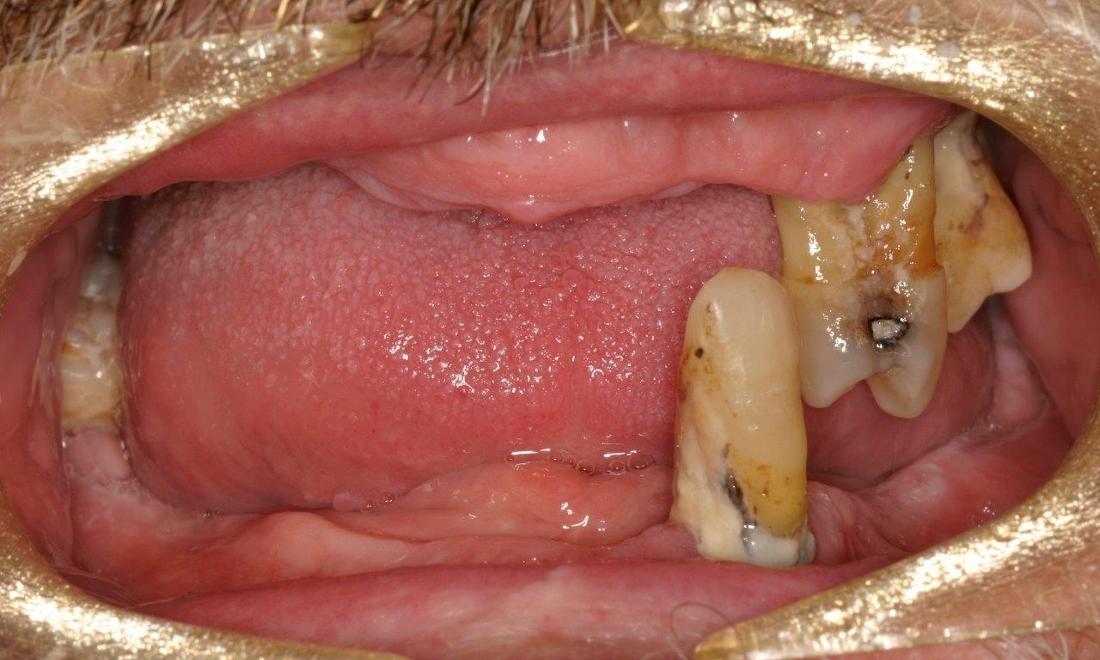

This patient was in need of a full smile makeover, and we were able to use dental implants to replace his missing teeth, and give him a new look.